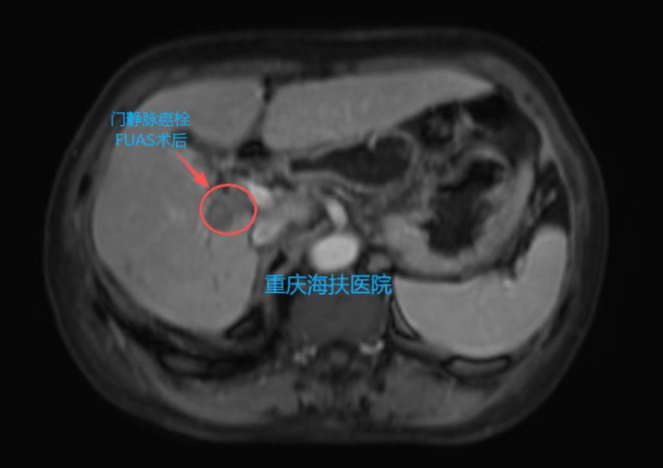

3月2日,张炼教授团队为患者实施全麻下聚焦超声消融治疗。一次性消融肝门淋巴结、肝脏病灶病变、门静脉癌栓,手术过程顺利。术后患者清醒,生命体征平稳,皮肤完好、无创口。

术后第1天,患者已进流食,无明显疼痛,仅轻微腹胀,复查指标整体平稳。复查MRI显示:消融区域肿瘤坏死明显,“黑洞”征清晰,提示病灶已被灭活。

此次治疗不仅灭活了肝内原发肿瘤,更成功处理了门静脉癌栓及转移淋巴结,充分体现了聚焦超声消融无创、精准、可一次性处理多处病灶的独特优势。